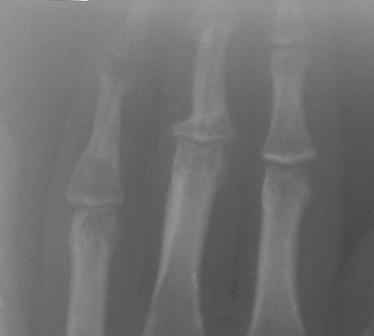

Уважаемые коллеги, на осмотре девочка 2006 г.рожд. Со слов матери 3мес. назад заметила припухлость основного фаланга 3-пальца, которая постепенно увеличилось до настоящего размера где-то в течении месяца, не болит, ребенка не беспокоит, признаки воспаления отсутствуют. Консультация онколога, биопсия - опухоль исключена (со слов матери), фтизиоортопед - тбс исключен. От основной фаланги 3 пальца к головке 4-пястной кости под кожей прощупывается хрящевидная ткань. Р-граммы от 10 декабря и 15 февраля, и фото прилагается. Что делать? Уважаемые коллеги, помогите! С уважением Абдурашид.

Добрый день, уважаемый Абдурашид. Судя по рентгенограмме, к сожалению не очень качественной, речь может идти о варианте дисхондроплазии, которую обозначают, как солитарную хондрому. Рентгенологически они проявляются в 3 вариантах-в виде интрамедуллярно и центрально расположенной энхондромы с вертеннобразным вздутием диафиза изнутри и истончением кортикальной пластинки, в виде опухоли, расположенной эксцентрично с заполнением части кортикального слоя и характерным костным козырьком, в виде экхондром, выступающих за пределы кости

Уважаемый Игорь Владимирович! Я очень рад Вас услышать! И в самом деле это один из вариантов дисхондроплазии ( т.н. болезнь Оллье), так как принесли результат биопсии: -"эмбриональный хрящевой ткань, симулирующий хрящевую опухоль"